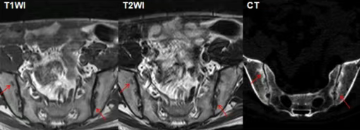

MR:可显示软骨下骨、韧带、滑膜和关节囊的软骨和急性炎症活动的初期变化,从而进行早期诊断。研究表明,MR在检测早期结构变化方面具有与CT类似的敏感性,并且对于评估脂肪沉积具有更好的灵敏度。MRI显示的骨髓水肿可为强直性脊柱炎的诊断及病情评估提供重要信息,且MRI现在正逐渐用于评估抗炎药物的疗效。

活动性炎症病变(早期改变)包括骨髓水肿,滑膜炎,关节囊炎,附着点炎。

结构性破坏(慢性改变)包括软骨下骨硬化,骨质侵蚀,关节周围脂肪沉积,骨桥、关节强直。